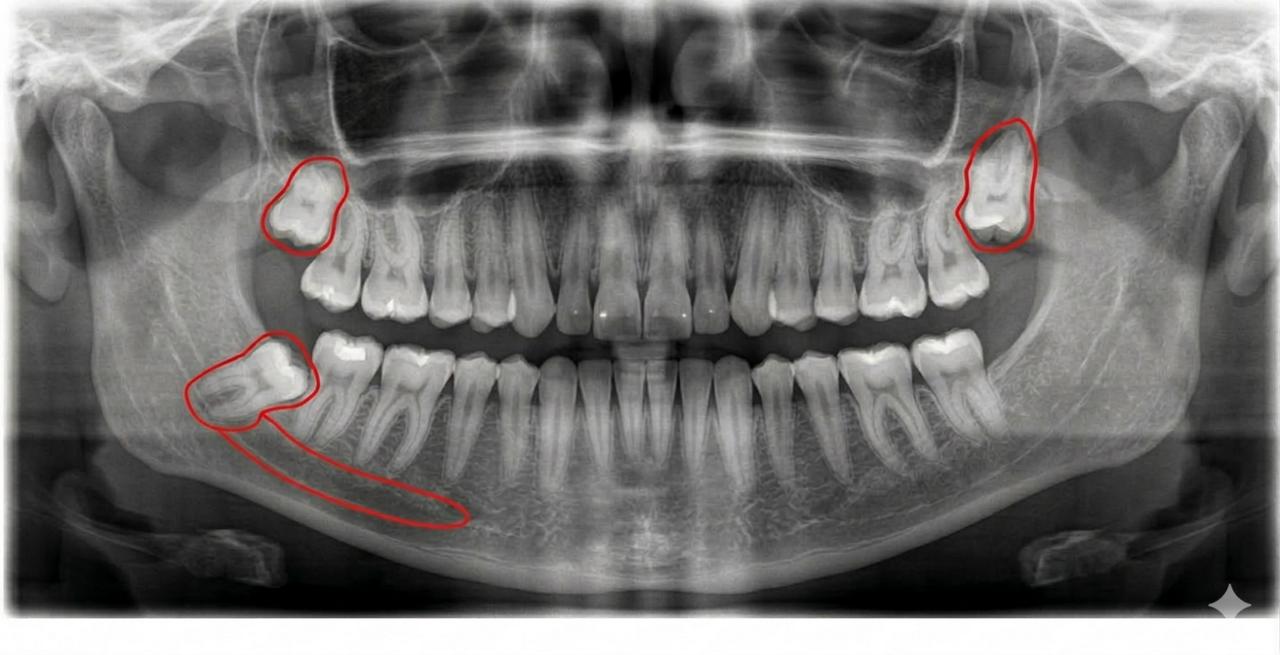

Діагностика та планування

Все починається з детального вивчення знімка. Хірург оцінює положення коренів відносно нервів та сусідніх зубів